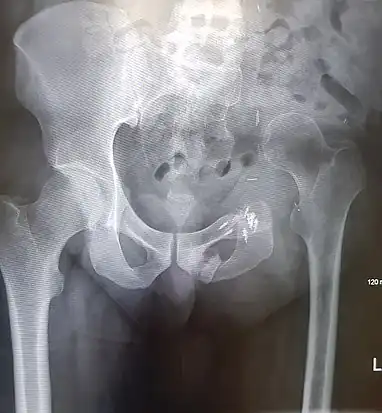

Intraoperative photograph after hemipelvectomy on the right side with view of the acetabulum. This was done for a case of gas gangrene.